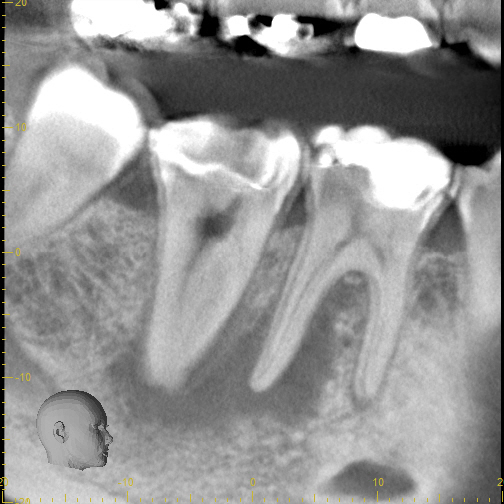

3_pre CBCT

8_recall 1 yr CBCT

Case 7

These images are from a 3D scan and show how important is a correct diagnosis. The pre-treatment image on the left shows what looks like two teeth with infections, but thorough testing showed that only one tooth needed treatment. The right image shows complete healing--around both teeth-- one year later. A careful diagnosis resulted in saving the adjacent tooth from unneeded treatment.